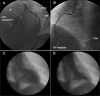

Biventricular apical thrombi demonstrated by contrast-enhanced cardiac MRI following anteroapical STEMI and unsuccessful reperfusion therapy

Contrast-enhanced cardiac magnetic resonance imaging can define the territory and extent of myocardial infarction from patterns of late gadolinium enhancement. Following failure to reperfuse with thrombolytic therapy, a case of myocardial infarction is described in which ongoing symptoms and an electrocardiogram change led to a diagnostic dilemma. Cardiac magnetic resonance imaging confirmed an apical infarction, an aneurysm and acute pericarditis. In addition, late gadolinium enhancement unexpectedly revealed the presence of biventricular apical thrombi. The prevalence of cardiac thrombi and pulmonary emboli may be greater than generally appreciated.